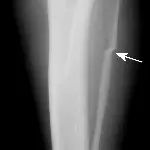

Figure 2A. The capital physis of this dog, which presented with hip pain, appears slightly widened.

Figure 2B. If the patient is positioned in a frog-legged position, the hairline fracture displaces and is easily diagnosed.